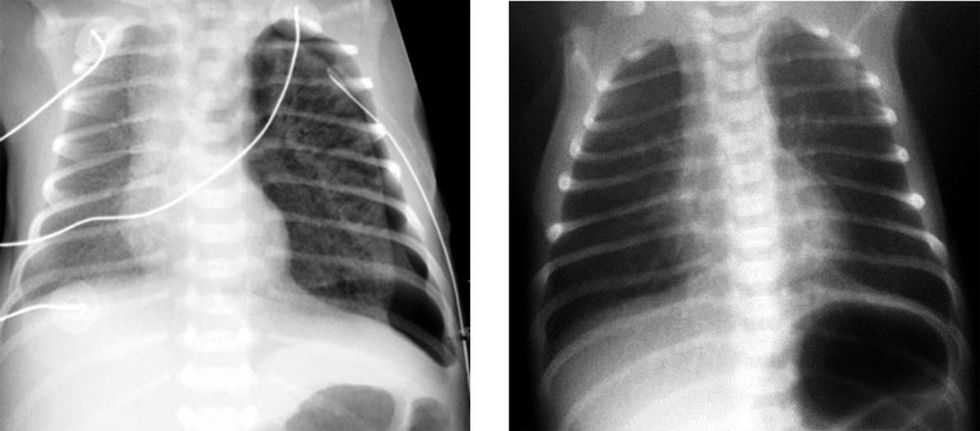

- Rtg-pulmo: hijezime të imta difuze